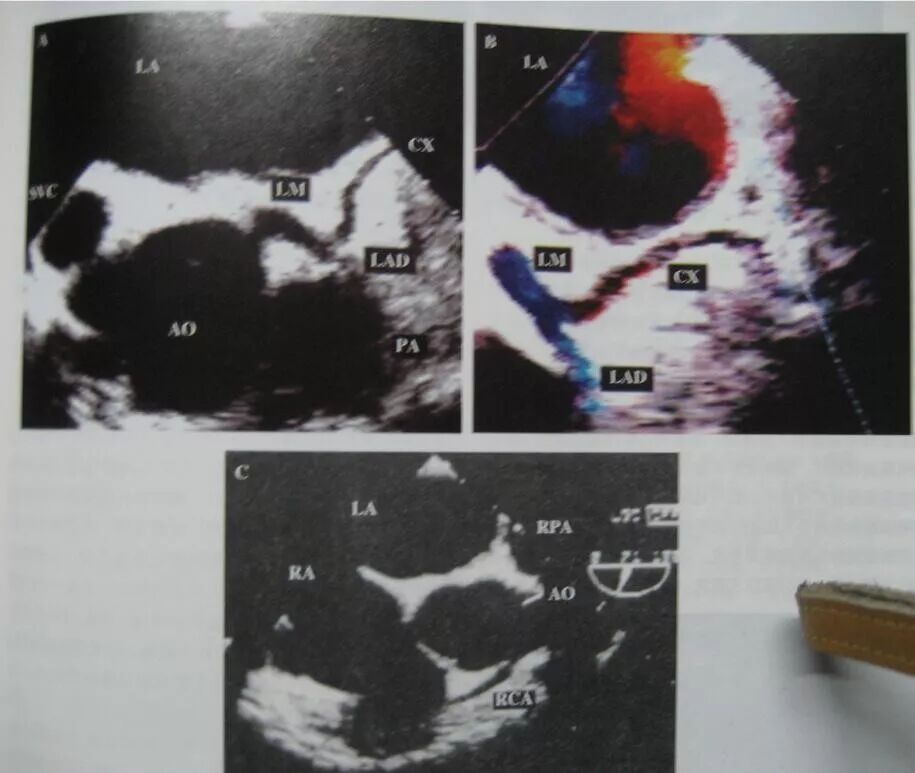

1.冠状动脉二维图像及血流

二维超声可显示较粗大冠状动脉如左右冠状动脉主干、前降支及左回旋支起始部的起源、走行、形态结构及血流状况。

胸骨旁心底短轴切面可显示左右冠状动脉开口,左冠状动脉开口位于主动脉根部4-5点处;右冠状动脉位于10点处。远端冠脉较难显示。

二维可测量冠脉管径、管壁厚度、有无斑块。多普勒超声可测量冠脉血流,血流频谱以舒张期为主,占2/3时间,收缩期占1/3时间。流速:舒张期30—80cm/s,收缩期12—20cm/s。